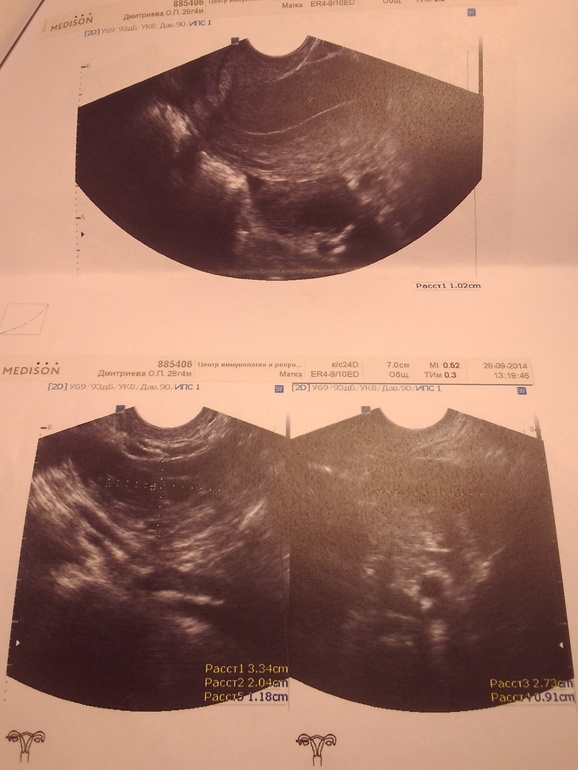

я совсем запуталась( продолжение вчерашнего поста) Два желтых тела!

По узи 2 желтых тела, а тест на овуляцию сегодня полосатый!ничего не понимаю!овуляция была или будет?

Вот решила картинки добавить, может кто разбирается!?

Никто мне не может объяснить откуда у меня 2 желтых тела((( если овуляция завтра, значит будет 3е желтое тело?капец!